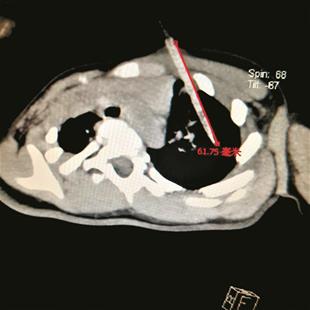

图为CT片显示,竹签扎进了肺部6厘米

该院心胸外科主任皮名安介绍,当时,患儿左胸上露在外面的竹签长约10厘米,上面还粘有一些残余的鸡柳肉,伤口处没有血流出。CT片显示,足有6厘米长的竹签从左胸前壁斜扎进了肺部,离心脏血管距离十分接近。情况危急,必须立马手术。“万幸的是,离心脏血管偏了一点点,一旦伤及心脏,患儿可能将失去救治机会。”皮名安主任介绍,拔出竹签后,肺部出现了漏气,消毒污染创面,缝合肺部破口,术后观察,未形成支气管胸膜瘘和肺部感染。昨日,小雅平安出院。